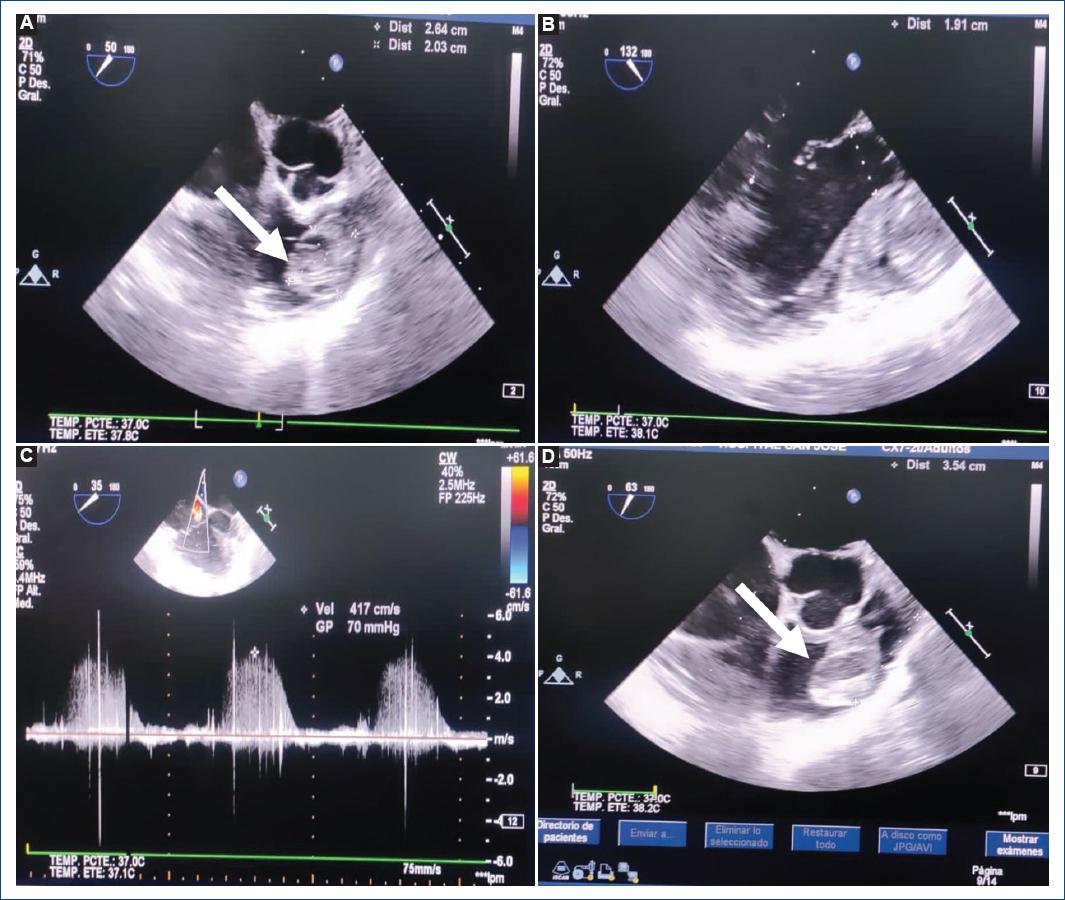

Figure 1 A-D: echocardiogram. Echocardiogram was performed showing an image of a cardiac mass with regular borders, high mobility toward the pulmonary valvular plane, circular in appearance (2.9 × 2.2 cm), with areas of echo-lucencies in its interior located (probable myxoma) in the right ventricular outflow tract causing functional pulmonary stenosis and severe right ventricle dilatation.

A 52-year-old woman presented with a history of hypothyroidism. She consulted for 8 days of atypical chest pain associated with decreased functional class (III/IV) and lower-limb edema, without syncope. She attended the emergency department where an echocardiogram was performed showing an image of a cardiac mass with regular borders, high mobility toward the pulmonary valvular plane, circular in appearance (2.9 × 2.2 cm), with areas of echo-lucencies in its interior located probable myxoma in the right ventricular outflow tract (RVOT) causing functional pulmonary stenosis and severe RV dilatation (Fig. 1). Cardiac magnetic resonance imaging shows a well-defined, pedunculated mass, arising from de RVOT, occupying 80% of the RVOT (36 × 32 × 20 mm), isointense on T1-weighted images (Fig. 2). CMR SSFP cine images show a well-defined, pedunculated mass, arising from de RVOT, occupying 80% of the RVOT, in contact with the inferior surface of the pulmonary valve. During images in systole, the mass moves through de valvular plane (Fig. 3), and the mass has heterogeneous enhancement during the perfusion images and T1-weighted images after gadolinium (Fig. 4).